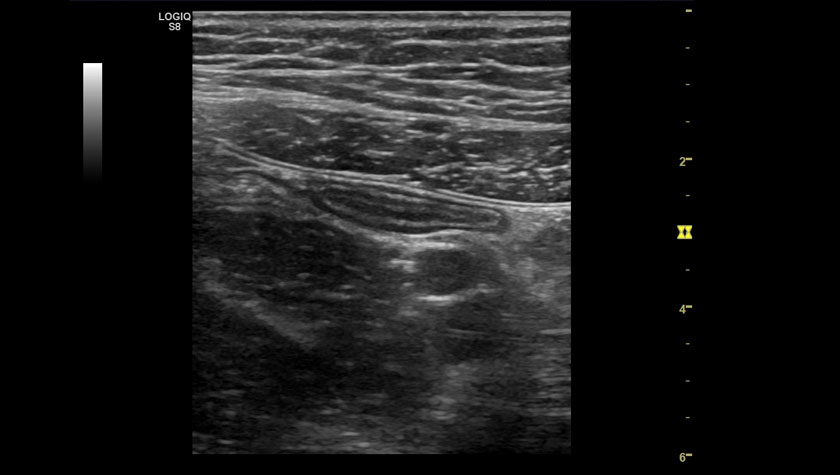

Печень, датчик C1-6-D

Аппендикс, датчик L3-12-D

Ахиллово сухожилие, датчик ML6-15-D

Молочная железа, датчик ML6-15-D

Эластография молочной железы, датчик ML-6-15-D